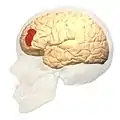

Brodmann area 46, or BA46, is part of the frontal cortex in the human brain. It is between BA10 and BA45.

BA46 is known as middle frontal area 46. In the human brain it occupies approximately the middle third of the middle frontal gyrus and the most rostral portion of the inferior frontal gyrus. Brodmann area 46 roughly corresponds with the dorsolateral prefrontal cortex (DLPFC), although the borders of area 46 are based on cytoarchitecture rather than function. The DLPFC also encompasses part of granular frontal area 9, directly adjacent on the dorsal surface of the cortex.

- Frontal view.